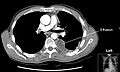

Chest computed tomography is more accurate for diagnosis and may be obtained to better characterize the presence, size, and characteristics of a pleural effusion. Lung ultrasound, nearly as accurate as CT and more accurate than chest X-ray, is increasingly being used at the point of care to diagnose pleural effusions, with the advantage that it is a safe, dynamic, and repeatable imaging modality.[7]

Massive left-sided pleural effusion (whiteness) in a patient presenting with lung cancer.